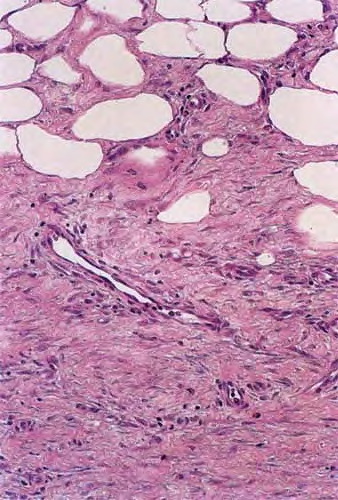

Histopathology. The histologic changes are present mainly in and near the septa of the subcutaneous tissue .

. The overlying dermis often has only a minimal to moderate, superficial and deep perivascular lymphocytic infiltrate.

In the early lesions of acute erythema nodosum, there is edema of the septa with a Iymphohistiocytic infiltrate, having a slight admixture of neutrophils and eosinophils . Focal fibrin deposition and extravasation of erythrocytes occur frequently  and can be revealed by spectral microscopy . Often, the inflammation is most intense at the periphery of the edematous septa and extends

into the periphery of the fat lobules between the individual fat cells in a lacelike fashion. Necrosis of the fat is not prominent. Rarely, clusters of neutrophils are present or the infiltrate is predominantly neutrophilic . Clusters of macrophages around small blood vessels, or a slitlike space, occur in early lesions and are known as Miescher's radial nodules . Some authors have failed to find central vessels  and have considered Miescher's nodules to be characteristic of erythema nodosum, stating that they can be found in all stages of erythema nodosum . The degree of vascular involvement is variable . Usually, there is edema of the walls of veins with separation of the muscular layers . Infiltration by lymphocytes is common, but neutrophils and eosinophils can be present as well. Necrosis of the vessel walls is very rare but has been observed in a few patients with lesions clinically indistinguishable from erythema nodosum . For example, focal vasculitis has been found in a few patients with acute erythema nodosum secondary to infections  and in a few cases of recurrent

Later lesions of acute erythema nodosum show widening of the septa, often with fibrosis and with inflammation at the edges of the septa and involving the periphery of the fat lobules . Neutrophils usually are absent, and the vascular changes are less prominent than in early lesions. There are more macrophages in the infiltrate. Macrophages at the edges of the fat lobules show phagocytosis of lipid from damaged adipocytes, and the small droplets of lipid in their cytoplasm give them a "foam cell" appearance. Granulomas formed by macrophages, without lipid deposition, are more frequent

when late lesions are compared with early ones . The granulomas often are loosely formed with macrophages predominating in a focus with multinucleated giant cells. Occasionally, well-formed, discrete sarcoidal granulomas occur in small numbers in the septa. The multinucleated cells usually have an irregular distribution of the nuclei in the cytoplasm. The oldest lesions have septal widening and fibrosis with a decrease in all of the inflammatory cells.